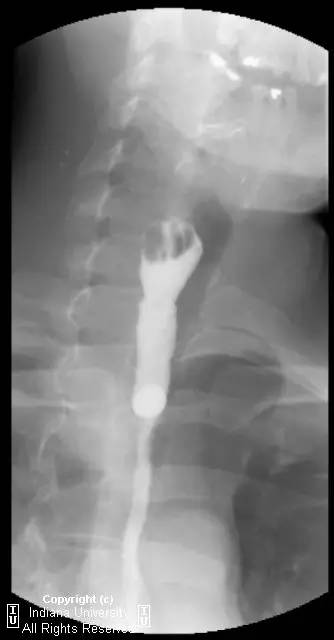

【影像学表现】下咽部正常,环咽肌功能正常。颈段食管无外生性病变压迫或异常扩张。胸中段食管长节段狭窄,逐渐移行为正常食管粘膜。大量小的烧饼样钡斑位于相应食管外呈浮萍样,与食管管腔无直接交通。稠或稀钡剂通过均无延迟。1cm钡剂片延迟通过,约30分钟后自动溶解。余食管动力正常。

【诊断】食管壁内假性憩室并长节段狭窄

Long segmentstricture with esophageal intramural pseudodiverticulosis

【关键点】食管壁内假性憩室